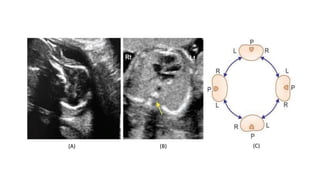

• #14 Figs A to C: Determination of the fetal right and left side by use of method described by Cordes et al. (A) The fetal head is aligned to the right of the screen The transducer is then rotated clockwise by 90° to obtain an image in the transverse plane at the level of the abdomen; (B) The spine is identified (yellow arrow), going clockwise from the spine is the right side followed by the left; (C) Showing diagrammatic representation that demonstrates the right and left sidedness according to the position of the spine in the transverse plane.